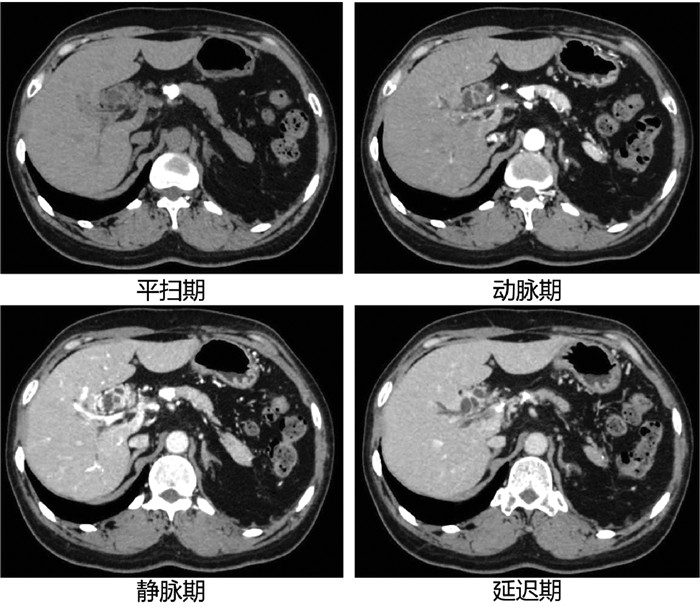

论著_肝脏肿瘤

经皮冷冻消融联合无水酒精注射治疗70岁以上老年肝细胞癌患者的效果及安全性分析

罗婧, 吕采红, 杨永平

2022, 38(2): 365-371. DOI: 10.3969/j.issn.1001-5256.2022.02.021

摘要(972) HTML (364) PDF (2738KB)(63)

摘要:

目的  探讨经皮冷冻消融(CRYO)联合无水酒精注射(PEI)对早期老年肝细胞癌患者的疗效和安全性。  方法  回顾性纳入解放军总医院第五医学中心2014年1月—2018年1月收治的92例老年肝细胞癌患者,其中单一CRYO治疗组46例,CRYO联合PEI(联合治疗)组46例。比较两种治疗方式的效果,不良反应及治疗前后肝功能相关指标的变化,并随访患者肿瘤的复发及生存预后情况。正态分布的计量资料两组间比较用t检验;非正态分布的计量资料两组间比较采用Mann-Whitney U秩和检验。计数资料两组间比较采用χ2检验。两组的生存时间采用Kaplan-Meier方法进行生存分析,并用log-rank检验生存曲线的差异;通过Cox回归法确定影响生存预后的独立危险因素。  结果  联合治疗组和CRYO组初次消融的有效率分别为89.1%和73.9%,组间差异无统计学意义(P>0.05)。CRYO组和联合治疗组患者术后总生存率和无瘤生存率间的差异均无统计学意义(P值均>0.05),但联合治疗组患者术后第1、2和3年局部肿瘤进展率分别为20%、21%和21%,明显低于CRYO组的30%、46%、46%(χ2=4.187,P<0.05)。多因素Cox回归分析提示行单一CRYO治疗可能是局部肿瘤进展率的独立危险因素(HR=2.206,95%CI: 1.003~4.850, P=0.049)。在不良反应的发生率上两组间差异没有统计学意义(P>0.05),但CRYO组有3例严重不良反应,联合治疗组未出现严重不良反应。  结论  对于早期老年肝细胞癌患者,CRYO联合PEI治疗较单纯CRYO治疗安全有效,能明显降低局部肿瘤进展率。